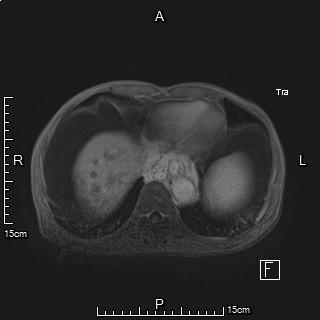

老年男性,诊断为原发性肝癌并门静脉癌栓形成,前期行肝动脉栓塞+放射性粒子植入治疗控制肝内病灶及门静脉分支癌栓。

术前MRI显示门静脉系统广泛癌栓形成,食管胃静脉曲张明显